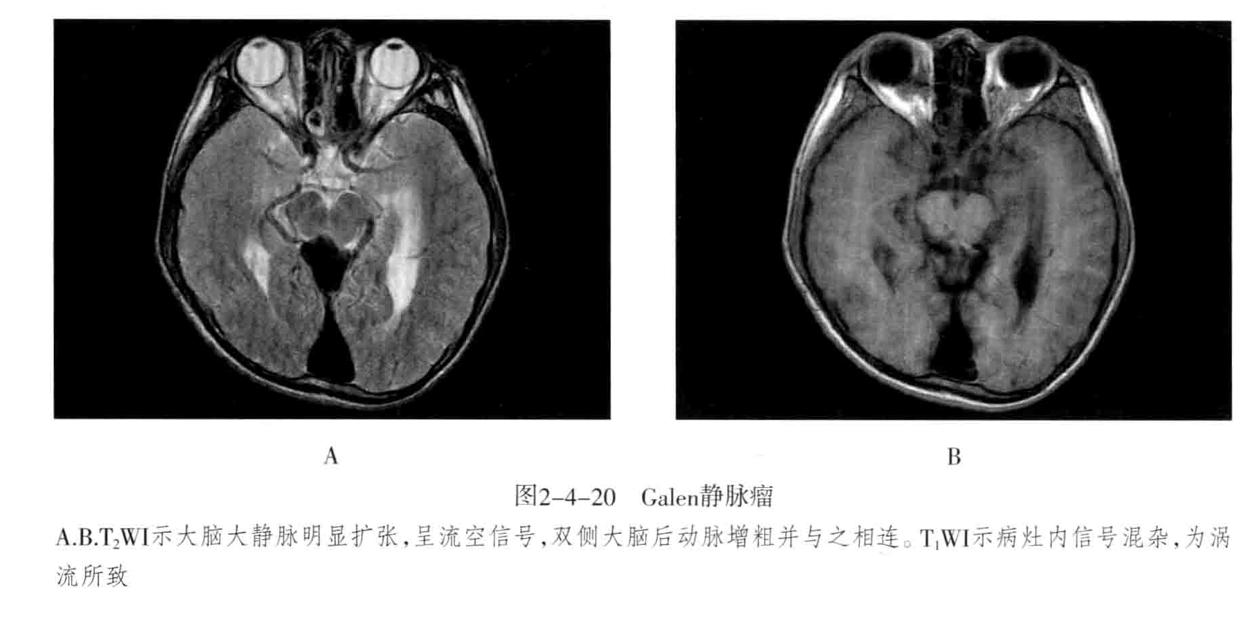

- 脑静脉性血管瘤 极为少见。静脉性血管瘤是一种组织上完全由静脉成分构成的脑血管畸形,任何年龄均可见,病理特点为许多放射状排列的扩张髓静脉连接成一条或多条扩张的经皮质或室管膜下引流静脉,最后汇入静脉窦。常发生于 额叶及小脑,以第四脑室周围多见 ,常伴发其他血管畸形,最常见为海绵状血管瘤。

- CT表现:平扫显示不清,周围无脑水肿,有时可见出血等改变,CTA典型表现为额叶或小脑许多细小髓静脉放射状汇入一条或几条引流静脉,最后汇入静脉窦,呈“水母头征”。

- MRI表现:可因病灶大小及血流速度不同而在MRI上呈多种信号,T1WI、T2WI多呈流空信号,少数由于血流缓慢也可呈略高信号,FLAIR呈低信号。增强后髓静脉及引流静脉明显强化,典型者呈“水母头征”,引流静脉可走向脑表面而引流至静脉窦,或走向脑室引流至室管膜静脉。MRV可显示引流静脉及其引流情况,但不显示髓静脉,SWI序列对本病显示很敏感。病灶周围无脑水肿表现,有时可见出血。